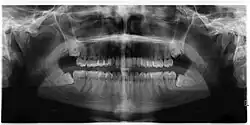

Las muelas del juicio retenidas se clasifican por la dirección de impactación, su profundidad en comparación con la superficie de mordida de los dientes adyacentes y la parte de la corona del diente que atraviesa el tejido gingival o el hueso. Las muelas del juicio impactadas también pueden clasificarse por la presencia o ausencia de síntomas y enfermedad. La detección de la presencia de muelas del juicio suele comenzar al final de la adolescencia, cuando una muela parcialmente desarrollada puede quedar retenida. La exploración suele incluir un examen clínico y radiografías panorámicas.

Si el diente no se puede evaluar únicamente con el examen clínico, el diagnóstico se realiza mediante una radiografía panorámica o una tomografía computarizada de haz cónico. Cuando las muelas del juicio no erupcionadas todavía tienen potencial de erupción, se utilizan varios factores predictivos para determinar la probabilidad de que los dientes se impacten. La relación de espacio entre la longitud de la corona del diente y la cantidad de espacio disponible, el ángulo de los dientes en comparación con los otros dientes son los dos predictores más utilizados, siendo la relación de espacio la más precisa. A pesar de la capacidad de movimiento en la edad adulta temprana, la probabilidad de que el diente se impacte puede predecirse cuando la relación entre el espacio disponible y la longitud de la corona del diente es inferior a 1.:[5] 141

No existe una norma para detectar las muelas del juicio. Se ha sugerido, a falta de pruebas que apoyen la retención o extracción rutinaria de las muelas del juicio, que la evaluación con radiografía panorámica, comenzando entre los 16 y los 25 años de edad, se realice cada 3 años. Una vez que exista la posibilidad de que los dientes desarrollen una enfermedad, se recomienda una discusión sobre los riesgos operativos frente al riesgo a largo plazo de la retención con un cirujano oral y maxilofacial u otro clínico capacitado para evaluar las muelas del juicio. Estas recomendaciones se basan en pruebas de nivel de opinión de expertos.[19] Puede ser necesaria la exploración a una edad más temprana si los segundos molares (los "molares de los 12 años") no erupcionan, ya que la posición ectópica de las muelas del juicio puede impedir su erupción. Las radiografías pueden evitarse si la mayor parte del diente es visible en la boca.